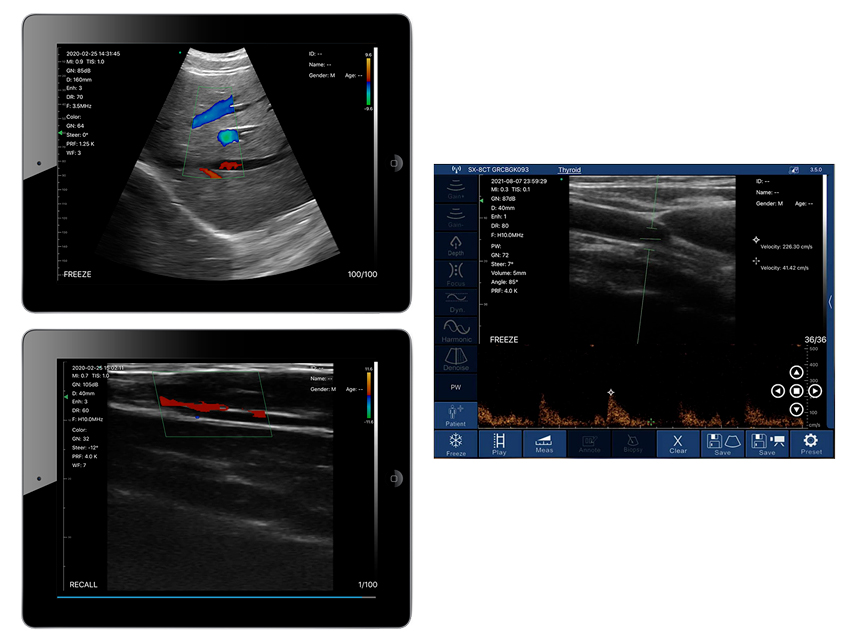

- Linear (VASCULAR / MSK / PEDIATRICS / BREAST / THYROID / CARotids / SMALL ORGANS)

- Frequency range (MHz): 7.5-10

- Convex (POLMONIES / ABDOMEN / CARDIOLOGY / GYNECOLOGY / OSTETRICIA / UROLOGY / RENI)

- Frequency range (MHz): 3.5-5

Linear probe: Examination of superficial organs such as breast, thyroid, lymph nodes, etc., and blood vessels such as carotids, arteries of the upper extremities, arteries of the lower extremities and other small organs, examination of musculoskeletal system.

Convex probe: abdominal and pelvic organ scan, FAST scan, pleural effusion scan and lung ultrasound.

Easy-to-use wireless portable ultrasound scanners, allowing the physician to manage the ultrasound results and share them with the patient with the appropriate software, anywhere, anytime.

Cases and reports can be saved and printed with a single click.

The high frame rate per second allows the smallest details to be obtained with maximum clarity, for rapid image-based diagnosis.

- wireless connection, compatible with tablets and smartphones (iOS, Android)

Built-in independent Wi-Fi module realises instant image transmission without external network, reduces data transmission delay and improves image clarity.

Scanning parameters (depth, gain, power and colour) adjustable with a simple and intuitive multi-key interface.

Doppler: B, B/M, B+Colour, B+PDI, B+PW